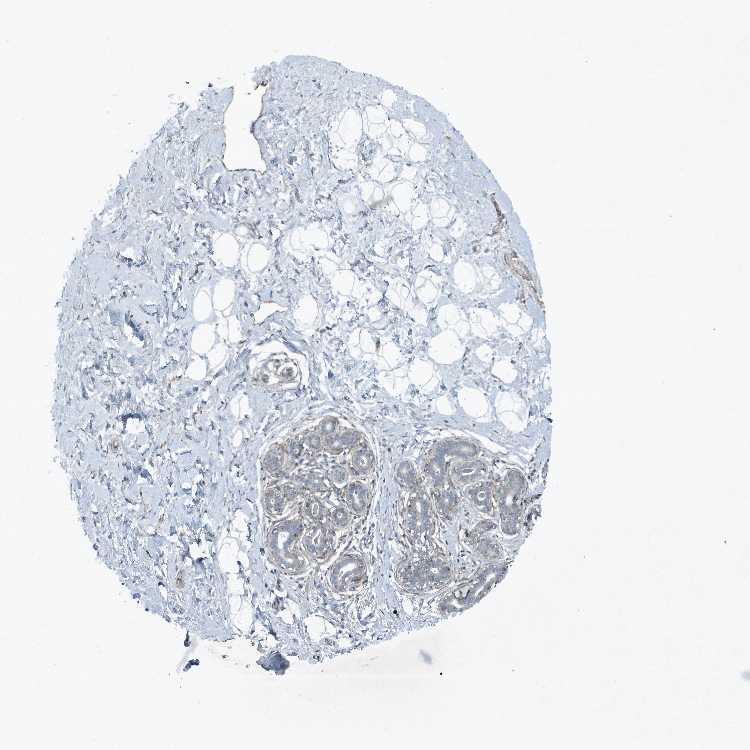

BREAST - Antibody stainingi

Antibody staining in the annotated cell types in the current human tissue is reported as not detected, low, medium, or high, based on conventional immunohistochemistry profiling in selected tissues. This score is based on the combination of the staining intensity and fraction of stained cells.

Each image is clickable and will lead to virtual microscopy that enables deeper exploration of all samples and also displays staining intensity scores, fraction scores and subcellular localization as well as patient and tissue information for each sample.

Antibody HPA046074Antibody CAB033822

Adipocytes Not detectedNot detected

Glandular cells LowNot detected

Myoepithelial cells Not detectedNot detected